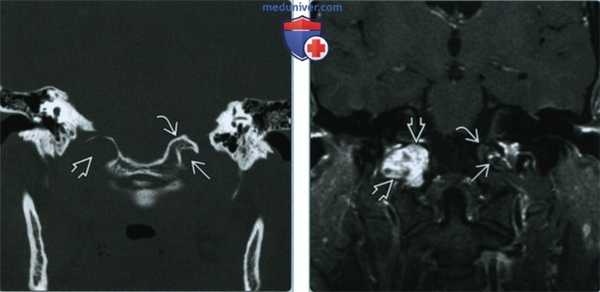

(Слева) При МРТ Т1 в аксиальной проекции наблюдается асимметрия сигнала языка. Правая половина языка не изменена; четко отграниченная левая половина языка дает патологически усиленный сигнал. Усиление сигнала свидетельствует о жировой инфильтрации и требует исследования канала подъязычного нерва.

(Справа) При МРТ Т1 с КУ в аксиальной проекции определяется дольчатое объемное образование левого подъязычного канала, распространяющееся в цистерну продолговатого мозга. Обратите внимание на отсутствие изменений правого канала подъязычного нерва. Отмечается равномерное контрастирование объемного образования, что характерно для шванномы. В ткани крупных опухолей часто наблюдаются кистозные изменения.

2. КТ при шванноме подъязычного нерва:

• КТ без контрастного усиления:

о Четко отграниченное объемное образование мягкотканной плотности по ходу ЧН XII

о В ипсилатеральной половине языка вследствие денервационной атрофии наблюдается коэффициент ослабления, соответствующий жировой ткани

• КТ с КУ:

о Однородное контрастирование ± интрамуральные кисты

• КТ в костном окне:

о Гладкостенный четко отграниченный расширенный КПН

о Корональная: увеличение размеров, перестройка нижней поверхности яремного бугорка (ниже «орлиного клюва»)

(Слева) При корональной КТ в костном окне наблюдается значительное расширение правого канала подъязычного нерва и эрозия нижней поверхности «орлиного клюва». Сравните наблюдаемую картину с левым каналом подъязычного нерва и яремным бугорком.

(Справа) При МРТ Т1 FS с КУ в корональной проекции у этого же пациента наблюдаются неравномерное контрастирование шванномы, выраженная фестончатость прилегающей затылочной кости и облитерация нормального «орлиного клюва»; те же изменения наблюдаются и на КТ. Слева определяются нормальный канал подъязычного нерва и яремный бугорок.